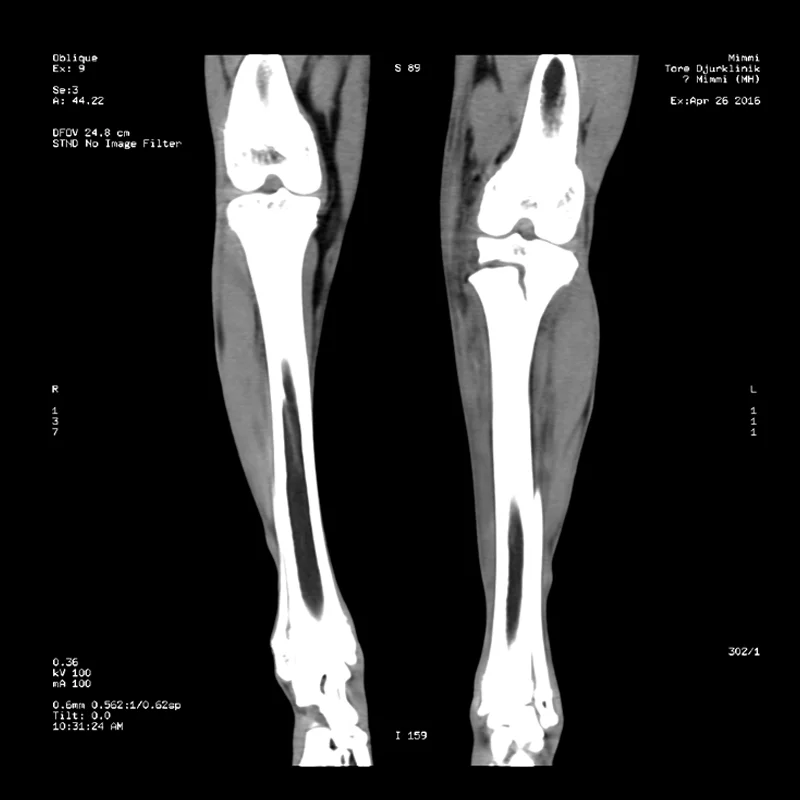

Fraktur Bakbenet

Denna Siberian Husky hamnade mellan skoter och pulka på fjället och bröt bakbenet i en tillväxtzon nära knäleden. Hon blev remitterad till Töre Djurklinik för CT undersökning och kirurgi. Vi skannade benet och opererade henne samma dag.